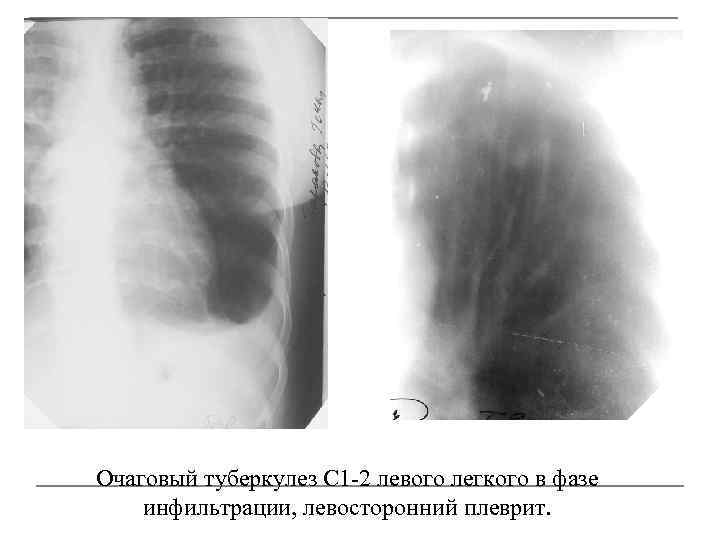

Иллюстрации по теме очагового и инфильтративного туберкулеза